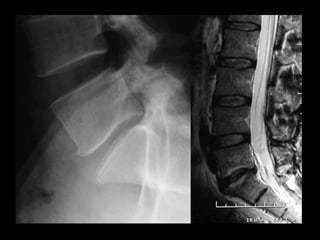

FUSION FOR LOWBACK PAIN Interbody fusion

remove the disc Interbody fusion • removethe pain source • stop the movement FUSION FOR LOW BACK PAIN